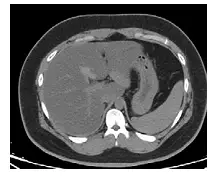

下圖為未注射對比劑的肝臟影像,最可能為那一項異常?

未注射對比劑(unenhanced)CT 判讀肝臟密度異常的基本原則:正常肝臟 Hounsfield unit(HU)約 55–65 HU,高於脾臟(~40 HU),因此正常肝臟在 CT 上應比脾臟更亮(高密度)。當肝臟出現脂肪浸潤,三酸甘油脂取代正常肝細胞,HU 下降,肝臟相對脾臟呈低密度(hypodense),即為脂肪肝(fatty liver / hepatic steatosis)的典型表現。

影像分析:

本題影像為未注射對比劑的腹部 CT 橫斷面,顯示上腹部截面。影像關鍵所見:

- 肝臟密度明顯降低:肝臟實質整體呈較深灰色調,密度低於正常預期值,與右側可見的脾臟相比,肝臟明顯較暗(hypodense),此為脂肪浸潤的直接 CT 表現

- 肝內血管相對明顯:因肝臟背景密度下降,肝內門靜脈分支相對呈高密度,形成「血管浮凸」現象(vascular prominence),是脂肪肝的間接特徵

- 病灶為瀰漫性:整個肝臟均勻低密度,非局灶性改變,支持瀰漫性脂肪浸潤(diffuse hepatic steatosis)

- 無局灶性病灶:未見明顯結節、腫塊或血管異常,排除局灶性病變

定量標準:Unenhanced CT 診斷脂肪肝的切斷值為:

- 肝臟絕對 HU ≤ 40 HU,或

- 肝脾 HU 差值